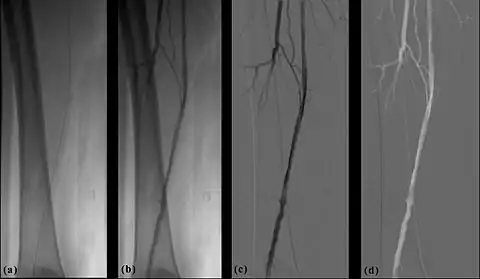

- The temporal-averaging feature of digital noise reduction can also be used for image presentation purposes so that the time course of the movement of contrast medium during a study can be displayed using just one image - see an example in Figure 7.4 from the peripheral study shown above - instead of a sequence of numerous images. Such an image is sometimes referred to as a Vascular Trace.

- One method of temporal filtration, referred to as Integrated Mask-Mode DSA involves adding (also called integrating) a number of images, acquired prior to the arrival of the contrast medium, to form an integrated mask image and adding a number of peak-opacification images to form an integrated live image. This is the process that was used to generate the vascular trace image in Figure 7.4. Thus, when four images are used to generate each integrated mask and live images, eight of the 25 images are now used in the subtraction process and, as a result, only 68% of the dose is wasted, and a subtraction image with lower noise results.

- Additional processes involve Bolus Chasing, Rotational Angiography and Volume Tomographic Angiography. Bolus Chasing[28] has been found to be particularly helpful in peripheral angiography, for example. Here, the progress of the contrast medium is tracked automatically and used to increment the table and/or XRT/image receptor movement to the next anatomical region. The subsequent set of subtraction images can then be used to construct a composite image of the peripheral vasculature. In Rotational Angiography[29], a C-arm assembly, for example, can be caused to rotate at 10 - 30 degrees per second during the imaging sequence. Subsequent dynamic display of the subtraction images can be used to generate a perceived 3D presentation so that complex relationships within the vasculature can be more readily appreciated. Volume Tomographic Angiography[30] is similar to Computed Tomography (CT) where the C-arm is rotated around the patient during the imaging sequence. The image data is subject to a volume reconstruction algorithm which permits generation of three-dimensional images of the opacified vasculature. We will consider this latter process in more detail below.